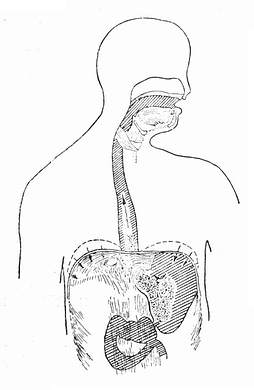

呕吐动作是复杂的生理活动(图37-1),既有体神经也有内脏神经参与,结果是将胃内容物排出体外。参加呕吐活动的有下述部分:唾液腺增加分泌,舌骨及喉头拉向前方,软腭上举,声门关闭,食管肌壁扩张,贲门部松弛,横膈强力收缩向下压迫胃,胃底部则松弛,腹壁肌肉,如腹直肌、腹外斜肌,腹内斜肌,有力收缩而向内压迫胃部,与胃贲门部松弛相反,幽门部收缩,所有上述动作协调起来,将胃内容物经食管从口排出体外。如动作不协调,例如食管上口环咽缩肌未松弛反而痉挛,结果造成食管内压力上升,由于胸膜腔压力小于食管内压力,导致食管破入胸膜腔内。上段及中段食管周围组织器官较多,有支持力,而下段食管周围少支持,成少最常见的破裂处。尚未见到奇静脉以上,主动脉弓以上水平食管破裂的报道。食管下段左右侧均可发生破裂,使食管内容物进入两侧胸膜腔。

呕吐动作的机理"/>

呕吐动作的机理"/>

图37-1 呕吐动作的机理